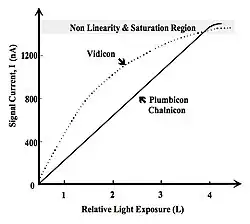

Subject contrast, developed by exposing the patient to an X-ray beam, is converted to image contrast on the display monitor. In general, this conversion is expressed by the Transfer Characteristic of the image receptor and can be obtained by plotting the radiation exposures necessary to generate a broad range of image receptor outputs. The transfer characteristic is generally linear in the case of CR and DR imagers, but this is not always so with XII-video systems. The XII itself generally has a linear characteristic, but some video cameras, e.g. the vidicon, may use a transfer characteristic which selectively boosts low exposure regions of images - see Figure 6.2. This type of behaviour is usually characterised by a power function which is expressed by what is called the camera's Gamma, γ, i.e.

where I is the signal current developed by the video camera when L is light exposure at its input and k is the electronic gain. In the case of the Plumbicon and Chalnicon, the gamma is close to unity, while for the vidicon its of the order of 0.7.